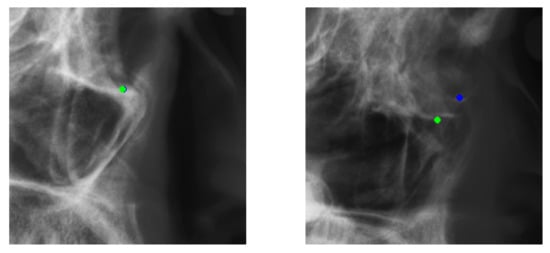

For registration, since people’s heads vary in shape, even though we selected the closest image to the training data as the reference image for each test image, there are still missed situations. This means that after the registration, the patch we created for the test does not include the ground-truth landmark. For the ISBI dataset, there is only one missed patch, and the rate is about 0.0002 (1/(19 × 250)), as presented in Figure 9. Overall, it has little impact on the results. For Testset2 of the ISBI Grand Challenge, we can see that Landmark 3, Landmark 6, Landmark 13, and Landmark 16’s have relatively low accuracy. However, the process works fine on Testset1. After we visualize the testing result, we find out that the anatomy of those failed cases are very different from the successfully detected ones. Since our training dataset has only 150 images, even though we did data augmentation, we still cannot deny the fact that people’s skeletal anatomies are so different that many types are not included in the training dataset. When we use our trained models to make predictions on those with huge anatomy differences, we will achieve unsatisfying results. We think this explains the poor performance on those landmarks in Testset2. We show an example in Figure 10.

Figure 9. Green point: test image’s landmark location. Red point: reference image’s landmark location. We can see that the green dot is not included in the bounding box we cropped.

Figure 10. Successful detection example from Testset1 and failed detection example from Testset2 on Landmark 3. Green points: predicted result. Blue points: ground-truth location.